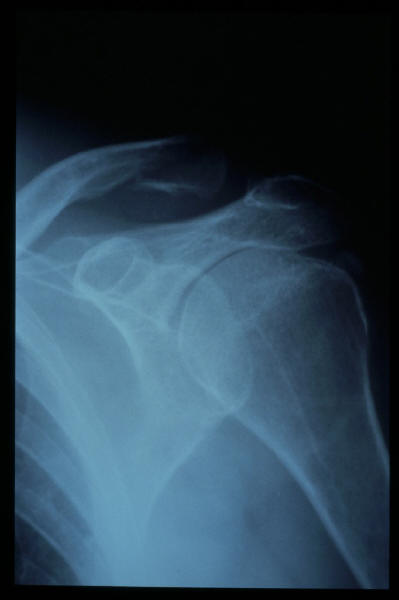

Fractura distal de clavícula

Fractura distal de clavícula.